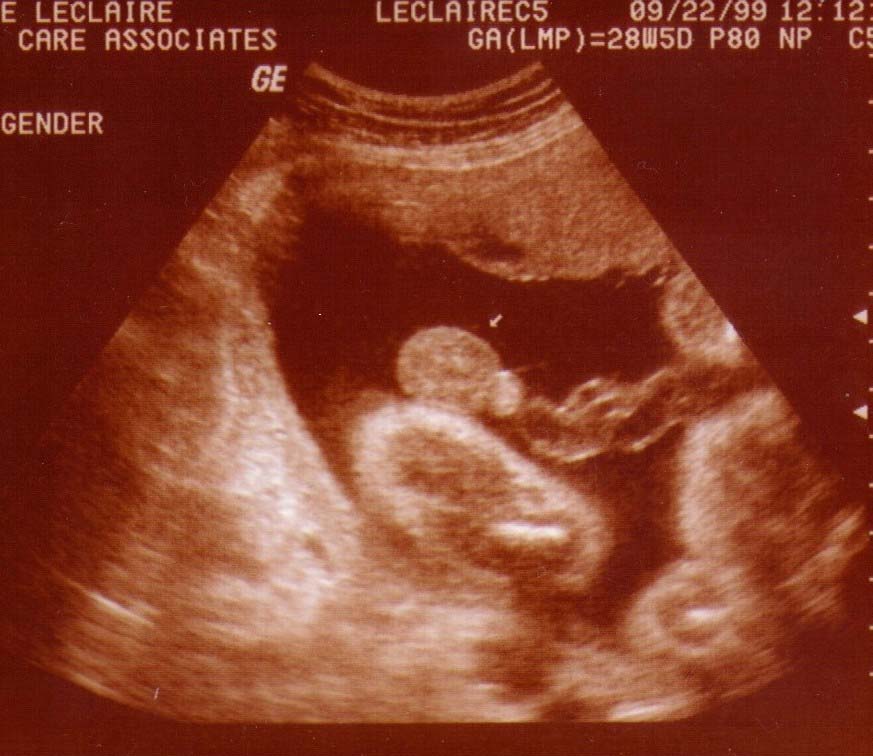

Alexander James LeClaire

Ultrasound Pics!

The Gender picture was right he's a boy!